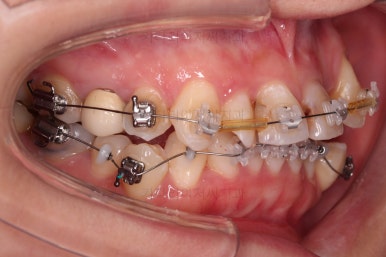

초진 시 입안의 모습입니다.

이미 썩어서 부러진 치아도 몇 개 보이고요.

많이 삐뚤어진 치아쪽은 양치가 힘들어 이미 많이 썩어 있는 상태에 덧니쪽은 잇몸도 많이 내려간 상태였습니다.

말그대로 교정치료 뿐만 아니라 전반적인 치료가 필요한 상황이었습니다.